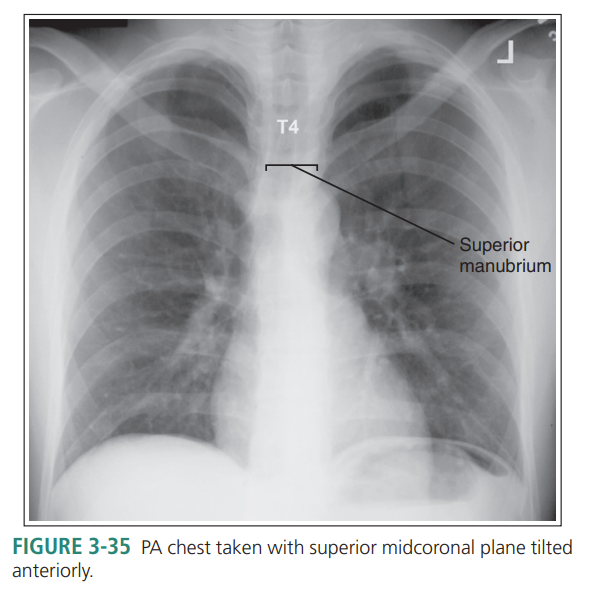

Superior midcoronal tilt anteriorly

Patient’s superior midcoronal is tilted anteriorly